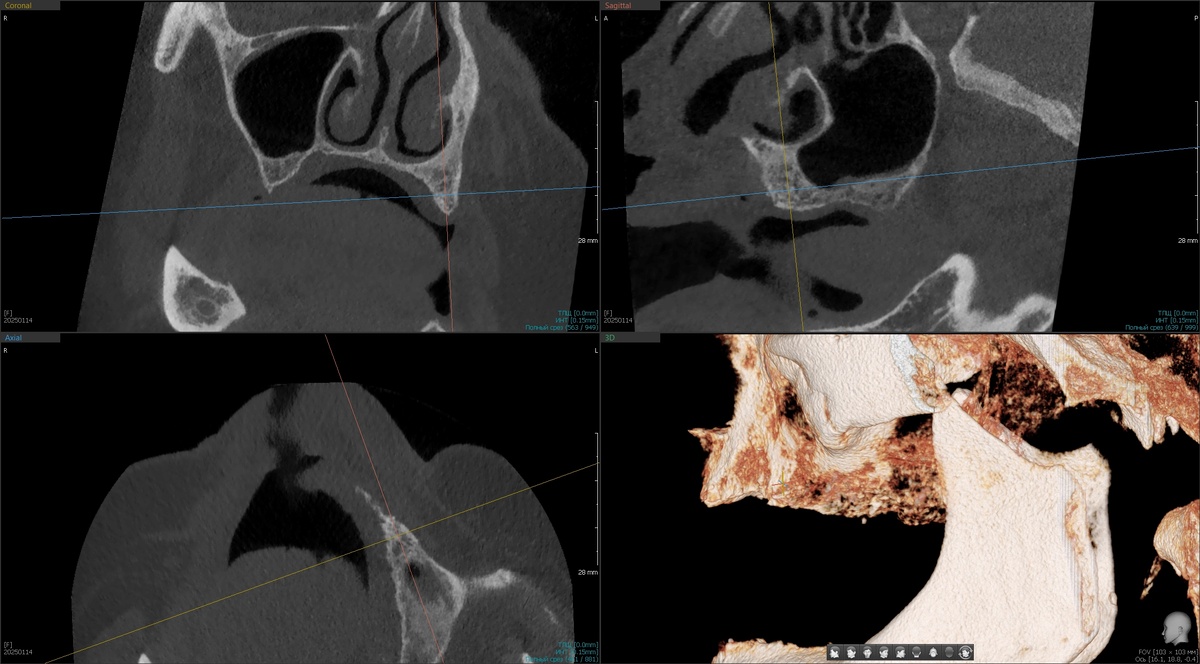

Дале оценка КЛКТ - есть ли место для имплантатов. На этом этапе, увы, с некоторыми пациентами приходится расставаться. Рассмотрим именно верхнюю челюсть, потому что с нижней проблем почти не бывает. Листайте:

Кости не очень много, но она есть и у доктора имеются интересные варианты для реабилитации.

Далее делаем КЛКТ с установленными в полость рта протезами и маячками:

Рентгеноконтрастные маячки, визуализация КЛКТ